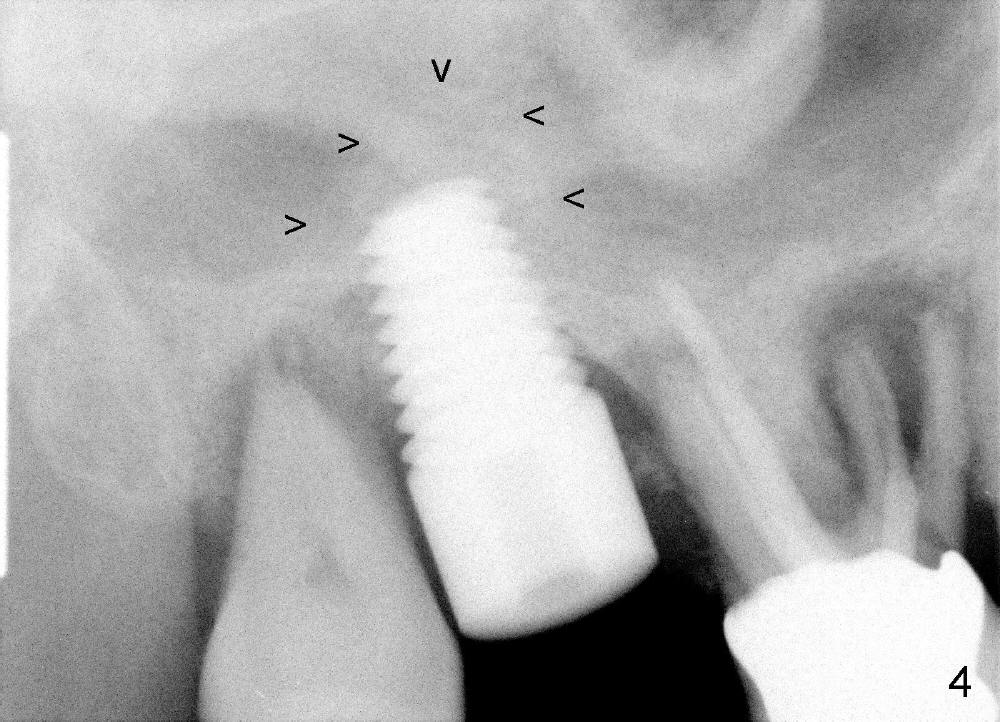

The upper right molars are deemed non-salvageable in a 60-year-old man (Fig.1). The tooth #2 is symptomatic. It is treated first. After extraction, osteotomes are used to create osteotomy (bone being solid) and sinus lift, followed by insertion of tap (Fig.2: 4.5x20mm). Arrowheads in Fig.2 indicate the upper border of the sinus floor. It appears that instrument is intruded too much into the sinus. Clinically the sinus membrane is perforated, as shown by nose blowing. The next bone manipulation instruments (taps 5-7 mm in diameter) should be shortened (17 mm). Fig3 shows a 7x17 mm tap in place with stability. Placement of 7x17 mm implant is associated with sinus lift (Fig.4 arrowheads).